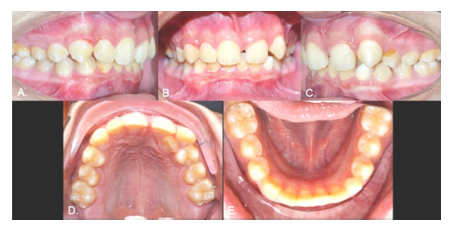

Case 1

Male, 12 years old. Clinical examination revealed that the inferior left canine was the only primary tooth still present (Fig. 1). The panoramic radiograph showed that the 3.3 was in a type 1 transmigration (Fig. 2A). The cone beam computed tomography (CBCT) showed that the crown of the transmigrated canine was very close to the adjacent incisors’ roots (Figs. 2 B and C). Despite the recommendation for surgical removal or even orthodontic traction, the parents chose not to treat the transmigrated tooth and instead to follow up with periodic radiographs.